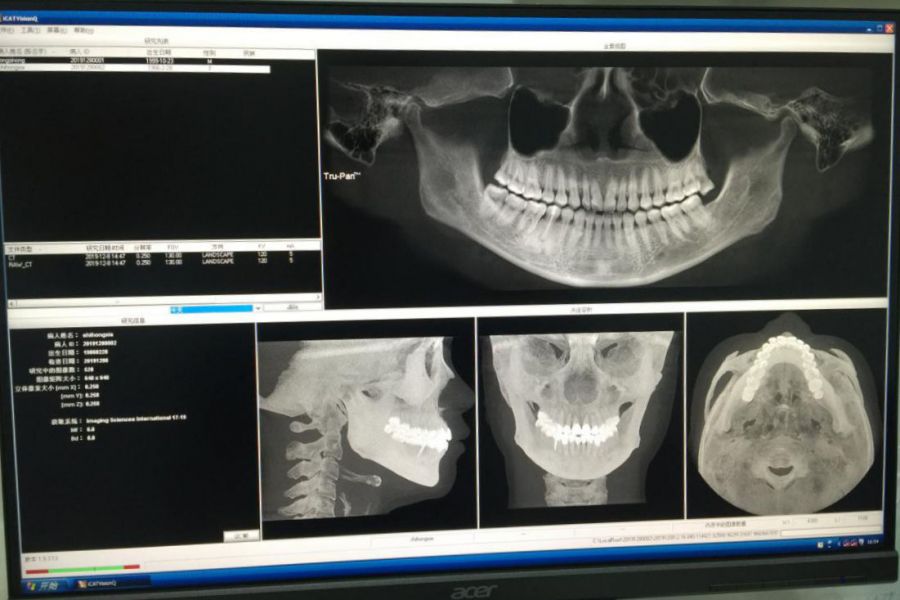

为提高口腔诊治水平,在医院领导的大力支持下,口腔科引进先进的卡瓦超大视野口腔锥束CT(简称CBCT),已于日前在口腔科门诊四楼完成安装调试,12月9日正式投入临床使用。

CBCT是目前国际先进的口腔科专用CT,具有扫描快、范围大、精度高、应用广,放射剂量极低的特点,可以通过其强大的处理软件功能以及面部匹配技术迅速形成清晰逼真的三维图像。“不忘初心、牢记使命”,本着全心全意为人民服务的理念,口腔科卡瓦超大视野口腔锥束CT投入使用后,将有利于疑难病例的诊治,从而更好的服务四省市边区人民群众。

卡瓦口腔CBCT计算机体层摄影设备

1.对牙齿及颌骨组织的结构成像质量更佳,可以清晰的观察牙根数目、根管的数目及形态,及时发现细小根管、根尖早期炎症及牙根折裂情况,还可以用它来测定牙周病的严重程度。对根管治疗的评估及正畸设计提供精准的诊断及治疗依据。

2.应用于阻生牙的拔除。通过CBCT成像,可以清楚显示智齿牙根与下牙槽神经管的关系,从而确定拔牙用力方向及牙齿脱位方向,尽量避免下牙槽神经损伤造成下唇麻木。

3.应用于种植修复领域。通过CBCT立体成像,细致观察缺牙区骨质的厚度及密度,从而精确知道种植体需要种植到什么位置、是否需要植骨或偏斜,从而协助医生的诊断及治疗,提高种植牙的成功率。

4.在颌面外科的应用。主要包括髁突磨损、囊肿、肿瘤的诊断及鉴别诊断、外伤、正颌手术的设计。